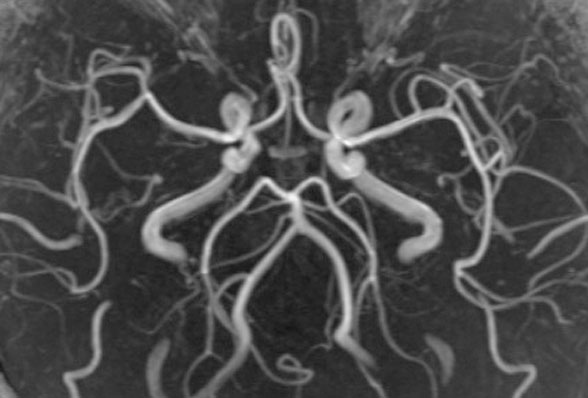

抗加齢ドック受診者における加齢と血管形態・機能解析

脳微小循環や血管形態と加齢による変化を検討します。また、MRA、頸動脈エコーなどによる血管形態評価と,認知機能,脈管機能や加齢による変化を解析します。